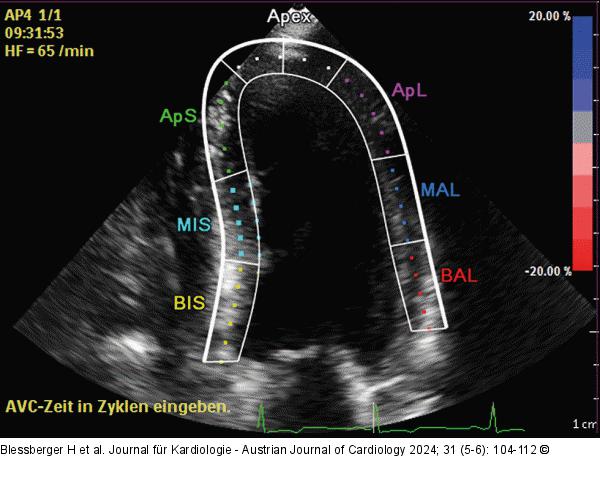

Abbildung 3: Echo Apikaler 3-Kammer-Blick optimiert für den linken Ventrikel mit Region of Interest (ROI). |

Apikaler 3-Kammer-Blick optimiert für den linken Ventrikel mit Region of Interest (ROI). |